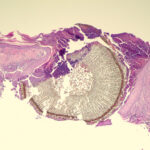

Foreign Body Reactions Foreign substances, when injected or implanted accidentally into the skin, can produce a nonallergic foreign-body reaction or, in persons specifically sensitized to them, an allergic response (. In addition, certain substances formed within the body may produce a nonallergic foreign-body reaction when deposited in the dermis or subcutis. Such endogenous foreign-body reactions are produced, for instance, by urates in gout and by keratinous material in pilomatricoma, as well as in ruptured epidermoid and trichilemmal cysts. |

Histopathology. A nonallergic foreign-body reaction typically shows a granulomatous response marked by histiocytes and giant cells surrounding foreign material. Often, some of the giant cells are of the foreign-body type, in which the nuclei are in haphazard array. In addition, lymphocytes are usually present, as may be plasma cells and neutrophils. Frequently, some of the foreign material is seen within macro phages and giant cells, a finding that of course is of great diagnostic value. The most common cause of a foreign-body granuloma is rupture of a hair follicle or follicular cyst, and sometimes only the cyst contents, rather than residual cyst wall, is identifiable . Exogenous substances producing nonallergic foreign-body reactions include silk and nylon sutures , wood or other plant material , paraffin and other oily substances, silicone gel, talc, surgical glove starch powder, and cactus spines. Some of these substances-nylon sutures, wood, talc, surgical glove starch powder, and sea urchin spines-are doubly refractile on polarizing examination. Double refraction often is very helpful in localizing foreign substances. Knife marks in the section may be an additional clue to the presence of particulate foreign matter |